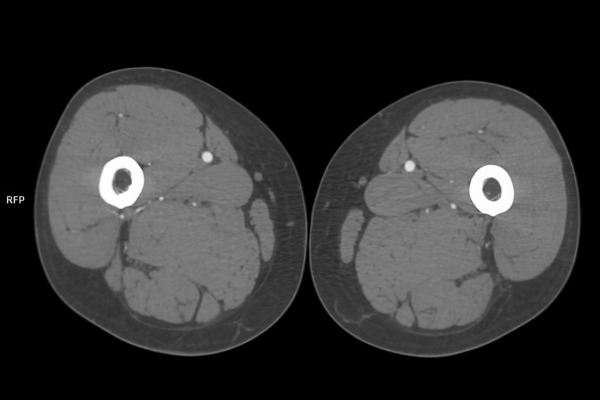

CT Untersuchung Bild